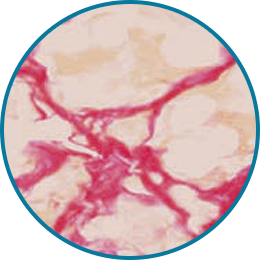

레디어스의 CaHA는 바이오 스티뮬레이터로

ECM 구성 성분 5가지를 만들어냅니다.

5가지 재생 성분은 약해진 피부 중심을 단단히 채워줍니다.

피부에 주입시켜 섬유아세포의 활성과 텐션을 회복하는 것은 바이오 스티뮬레이터인 레디어스의 가장 큰 특징입니다.

피부 탄력성, 두께감, 피부결 개선

조직회복, 콜라겐 1형의 구조적 지지

피부 탄력성, 피부 탄탐함

수분 보충, 피부 탄탄함

혈액 공급, 영양분 공급

시술 직후, 피부와 주변 조직이 건강하게 재생되기 시작하고 콜라겐을 비롯한 탄력 성분들이 자연스럽게 활성화되며 피부 세포의 기능이 점차 정상화됩니다.